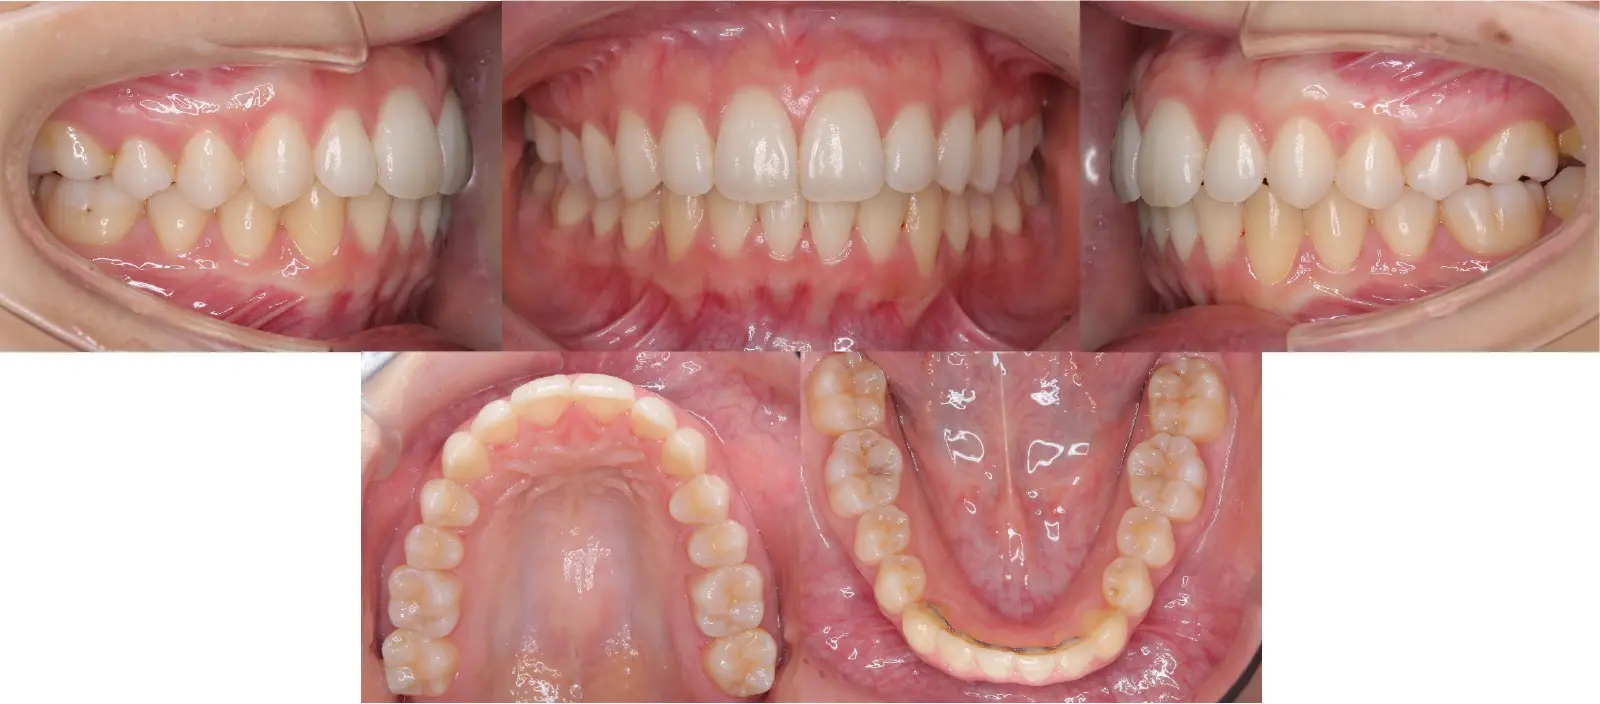

- 主訴

乱杭歯、八重歯

- 年齢

10代

- 治療期間

1年8ヶ月

- 治療回数

19回

- 治療に用いた主な装置

カスタムメイド型マルチブラケットタイプのデジタル矯正装置(インシグニア)

- 治療費

600,000円(税別)、調整料5,000円(税別)

※伊那分院にて治療

- 抜歯部位

上顎第一小臼歯2本

下顎右第二小臼歯1本、左第一小臼歯1本